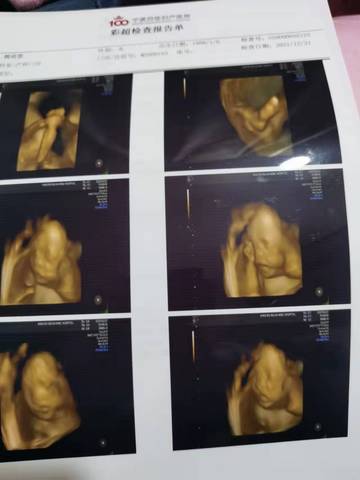

各位大神谁知道男孩女孩,就是好奇????

journal_insert_pic_1684053392journal_insert_pic_1684053402

可爱的孕妈,我们都是一样觉得好奇,这个确实没啥依据可参考的,就算B超有图片也只是一个宝宝的轮廓,心想事成!

亲爱的,通过这些判断不出来是什么样性别的哈,反正宝宝发育好就是最好的哈,祝你好孕。